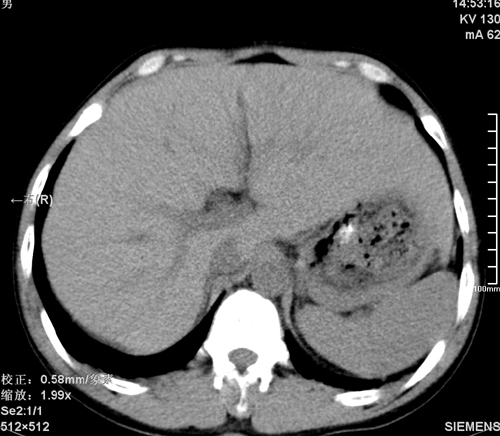

以下是引用tao772在2008-3-28 12:29:00的发言:[br]右侧腹膜后积血,右侧腰大肌挫伤,右侧部分横突骨折. 肾脏最好报一下挫伤,必要时增强。